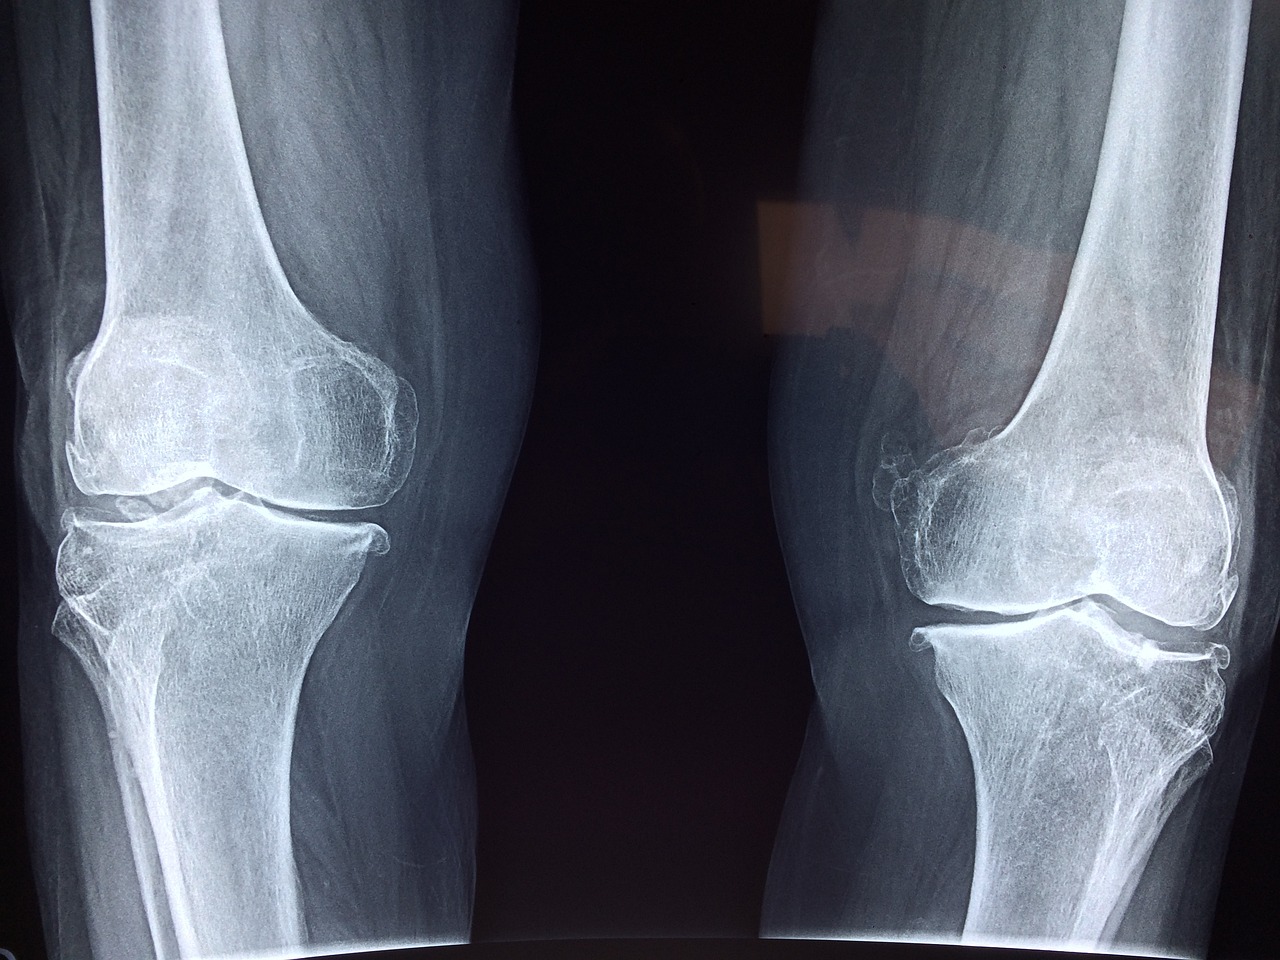

무릎 인공관절 수술을 받은 후 통증이 남아 있는 건 자연스러운 회복 과정일 수 있습니다.

하지만 특정한 신호가 동반된다면 단순한 수술 후 통증이 아닌 무릎 인공관절 수술 후 염증일 가능성도 있습니다.

1️⃣ 무릎 인공관절 수술 후 정상적인 회복 과정

✅ 무릎 인공관절 수술 후엔 어느 정도의 통증과 부기가 따라오는 것이 일반적입니다.